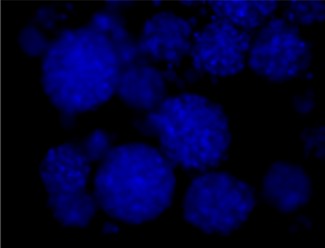

Immunofluorescence staining of Src and Phospho-Src

DAPI

Merged